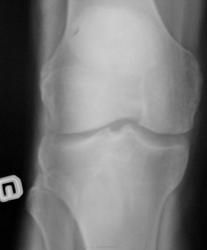

Случай №2 Женщина ,50 лет пришла на снимок коленных суставов на предмет ДОА. Снимки сделали. И у меня возник вопрос. На боковых снимках последствия болезни О.-Шлаттера? Или это обычное обызвесвление связок?

Случай №2. Это ещё называют тендинозом. Обызвествление связки надколенника. Причина: микротравмы.